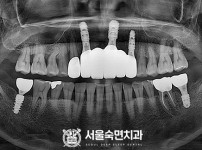

임플란트-전후사진3

치과를-선택할-때-꼭-확인하세요-서울숙면치과-임플란트-전후사진